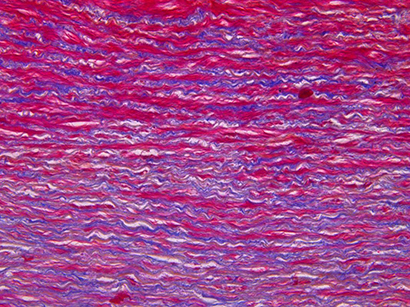

Specimens for brightfield microscopy commonly have to be stained e.g. with Hämatoxylin-Eosin (H&E). This is a part on an aorta (20x).